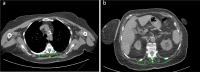

Background Lower muscle mass is a known predictor of unfavorable outcomes, but its prognostic impact on patients with COVID-19 is unknown. Purpose To investigate the contribution of CT-derived muscle status in predicting clinical outcomes in patients with COVID-19. Materials and Methods Clinical or laboratory data and outcomes (intensive care unit [ICU] admission and death) were retrospectively retrieved for patients with reverse transcriptase polymerase chain reaction-confirmed SARS-CoV-2 infection, who underwent chest CT on admission in four hospitals in Northern Italy from February 21 to April 30, 2020. The extent and type of pulmonary involvement, mediastinal lymphadenopathy, and pleural effusion were assessed. Cross-sectional areas and attenuation by paravertebral muscles were measured on axial CT images at the T5 and T12 vertebral level. Multivariable linear and binary logistic regression, including calculation of odds ratios (ORs) with 95% CIs, were used to build four models to predict ICU admission and death, which were tested and compared by using receiver operating characteristic curve analysis. Results A total of 552 patients (364 men and 188 women; median age, 65 years [interquartile range, 54-75 years]) were included. In a CT-based model, lower-than-median T5 paravertebral muscle areas showed the highest ORs for ICU admission (OR, 4.8; 95% CI: 2.7, 8.5; P < .001) and death (OR, 2.3; 95% CI: 1.0, 2.9; P = .03). When clinical variables were included in the model, lower-than-median T5 paravertebral muscle areas still showed the highest ORs for both ICU admission (OR, 4.3; 95%: CI: 2.5, 7.7; P < .001) and death (OR, 2.3; 95% CI: 1.3, 3.7; P = .001). At receiver operating characteristic analysis, the CT-based model and the model including clinical variables showed the same area under the receiver operating characteristic curve (AUC) for ICU admission prediction (AUC, 0.83; P = .38) and were not different in terms of predicting death (AUC, 0.86 vs AUC, 0.87, respectively; P = .28). Conclusion In hospitalized patients with COVID-19, lower muscle mass on CT images was independently associated with intensive care unit admission and in-hospital mortality. © RSNA, 2021 Online supplemental material is available for this article.

Figures